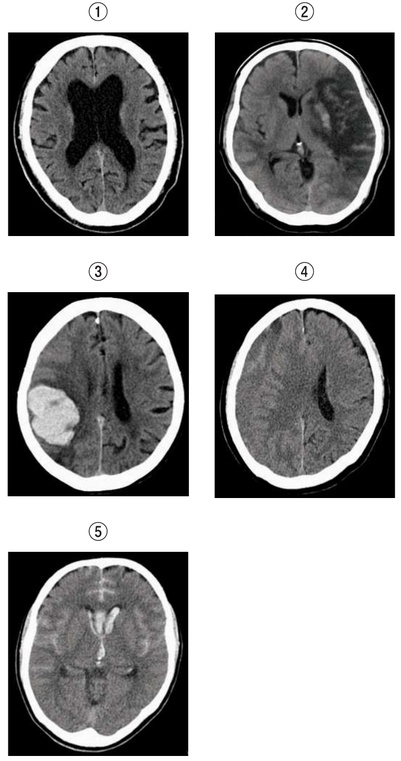

68歳の女性。2か月前に頭部打撲歴あり。10日前から歩行障害が出現し徐々に悪化した。病院を受診したところ緊急入院となった。穿頭血腫ドレナージ術後、症状は改善した。別に示す頭部CT画像 のうち、この患者の術前の頭部CT画像はどれか。

1

①

2

②

3

③

4

④

5

⑤